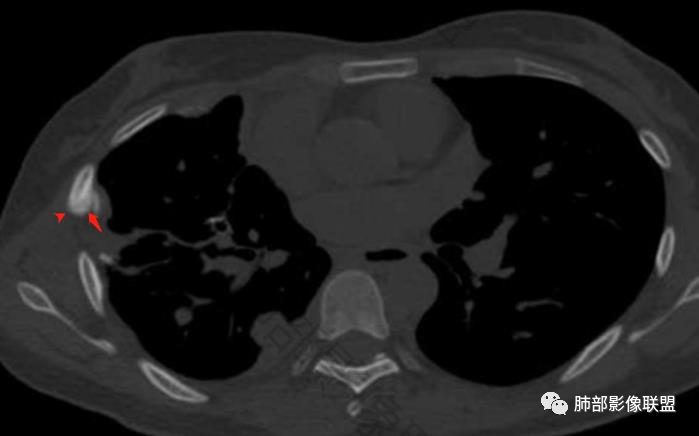

这个骨窗很有价值

价值就在于这个密度

骨质破坏,但是密度增高

你对比一下髓腔

它这个髓腔密度不对,皮质也欠连续,还是以骨头为主

南边:那就是说这个肋骨是自身的病变,有成骨性骨质破坏

从这个角度区看肺部/胸膜的病变,想法就不一样

肋骨伴随有溶骨性/成骨性骨质破坏,常规还是要警惕恶性